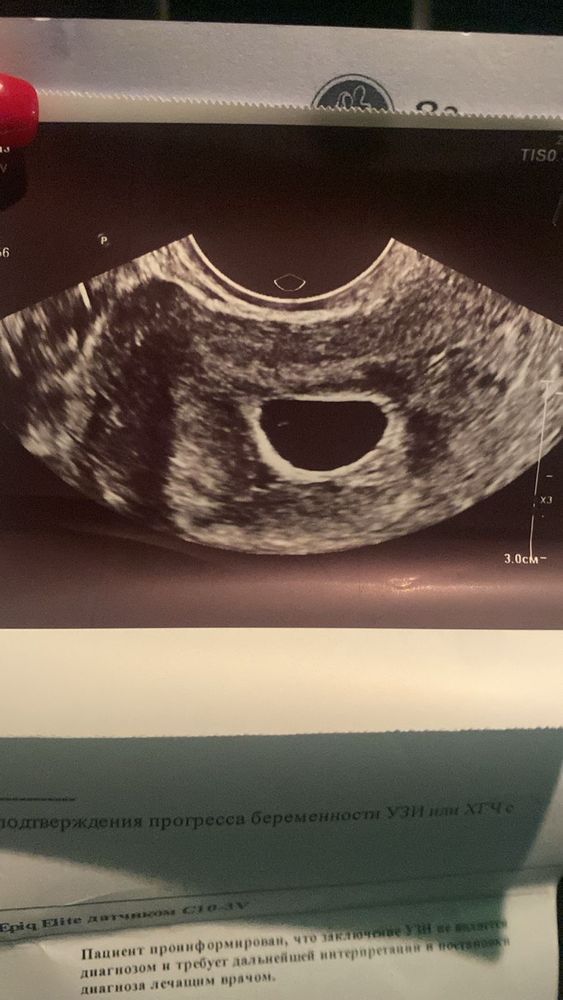

Марина, это не мое узи🙈 подруги, просто не знаю как ее успокоить, сама понимаю что это конец, может у девочек тут были положительные исходы которые дадут надежду. у нее все верно по сроку вот первое узи 03.11 посмотрите пожалуйста, прошло уже 3 недели с первого узи, сколько еще нужно подождать пока появится Изображение

Марина, 2.11 числа хгч был-1544,91 3.11 числа УЗИ- ПЯ 6мм И вот переделала вчера узи, не знаю даже какие тут шансы

Не хочу внушать надежду но, может через пару дней еще раз глянуть? Все таки есть желточный мешочек.. обычно до 25мм ждут когда ПЯ будет Сама в похожей ситуации сейчас Находила разные случаи Один из Изображение Изображение

kna1992, 18мм не большое без ктр?

УЗИ в 7 недель и 2 дня УЗИ ОМТ